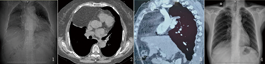

例1 女,70岁。因间断干咳6年入院。无恶心呕吐,无腹痛,近1年干咳较前加重。X线胸片示右膈位置类圆形密度影(图1)。CT示前纵隔右侧心膈角旁见类圆形纯脂肪密度影,边界清楚(图2)。增强CT示右侧心膈角膈肌连续性中断,胸骨后心膈角旁见类圆形纯脂肪密度影,大小约9.8 cm×6.2 cm,边界清楚,其内见走行血管影来源于腹腔血管,考虑Morgagni疝(图3)。

例2 女,57岁。因上腹疼痛2个月入院。上腹部呈阵发性钝痛,恶心无呕吐;B超示胆囊多发息肉,胆囊结石。X线胸片示右膈位置略显抬高(图4)。